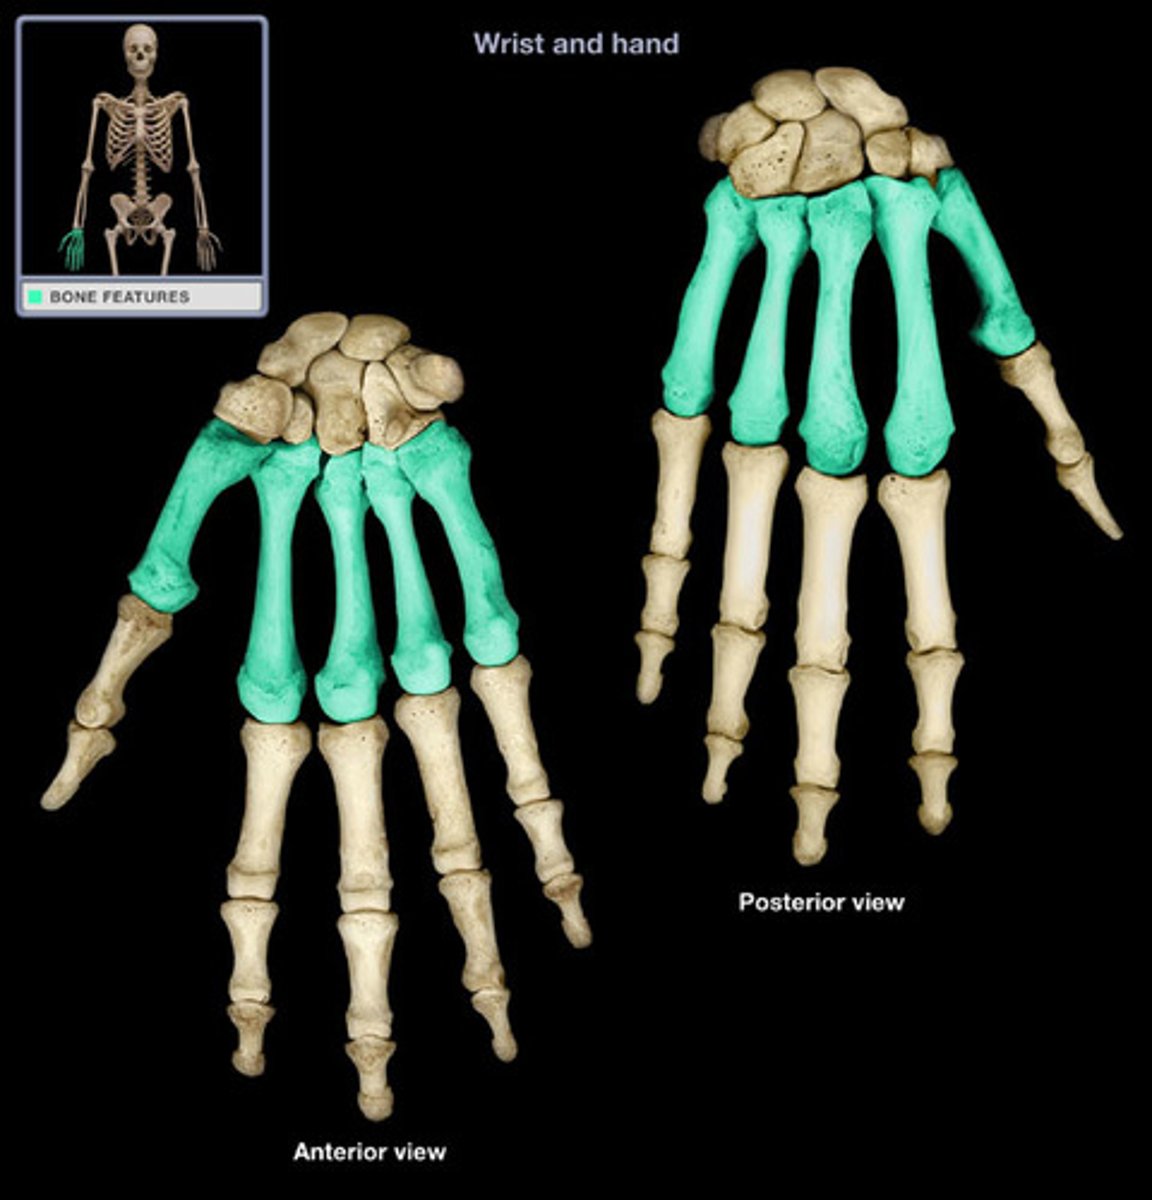

Carpus

The proximal end of our 'hand'. This is the true wrist

8 sets of bone in 2 rows by 4 columns

Carpals

The 8 short bones which are located in the carpus

Scaphoid

A large carpal bone articulating with the radius below the thumb

Lunate

The bone immediately medial to the scaphoid. Connects to the radius

Triquetral

The third bone in the proximal row counting from the lateral side. Articulates with the lunate, hamate and pisiform

Pisiform

The bone in the proximal row that is the most medial

Trapezium

The distal bone immediately below the thumb.

Trapezoid

The bone immediately medial to trapezium. Articulates with the index finger metacarpal.

Capitate

The largest carpal bone that articulates with the third metacarpal

Hamate

Situated on the lower outside edge of the hand. It has a hook-shaped projection on the palmar side to which muscles of the little finger are attached.

Metacarpus

The palm of the hand. The bones are numbered 1-5 from medial to lateral. The bases articulate with the carpals and each other laterally.

The head are the knuckles when you clench your fists.

Phalanges

The fingers of the hand. Numbered 1-5 from medial to lateral.

Sans the thumb, each finger has 3 phalanges: distal, middle and proximal.

The thumb has no middle phalanx.